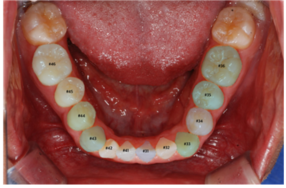

이미지/라벨링 예시

| 이미지 | 라벨링 | |

|---|---|---|

| lower |

치아경계